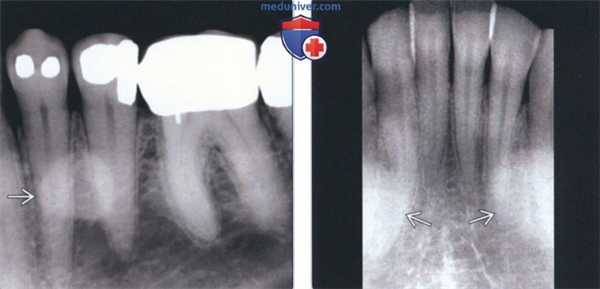

• Интраоральные рентгенограммы:

о Хорошо отграниченный, ровный рентгеноконтрастный участок в альвеолярном отростке без периферического просветления

(Слева) На периапикальной рентгенограмме определяются едва заметные рентгеноконтрастные участки возле шеечного края передних зубов. Эти выбухающие участки, чаще возникающие на нижней челюсти, носят название щечной «губы». Клинические они выглядят как маленькие бугорки под нормальной слизистой оболочкой.

(Справа) На аксиальной 3D КЛКТ визуализируются множественные экзостозы с щечной стороны верхней челюсти в области моляров и премоляров. Столь многочисленные экзостозы можно удалить, т.к. они способны привести к функциональным нарушениям. Видна также щечная «губа» в передних отделах верхней челюсти.

2. Рентгенография при небном валике:

о Хорошо отграниченные рентгеноконтрастные участки, которые могут накладываться на изображение верхнечелюстной пазухи на периапикальных рентгенограммах задних зубов

(Слева) На периапикальной рентгенограмме области средней трети корней премоляров слева определяется четко отграниченный рентгеноконтрастный участок. Такая локализация типична для нижнечелюстных валиков, хотя валики большого размера могут распространяться кзади к молярам и кпереди к резцам. Обратите внимание на отсутствие просветления на периферии. Четкие и ровные края помогают отличить валик от идиопатического остеосклероза.

(Справа) На периапикальной рентгенограмме центральных резцов нижней челюсти определяются типично выглядящие двухсторонние нижнечелюстные валики.

3. Рентгенография при нижнечелюстном валике:

о Двухсторонние хорошо отграниченные рентгеноконтрастные участки в области средней трети корней премоляров нижней челюсти